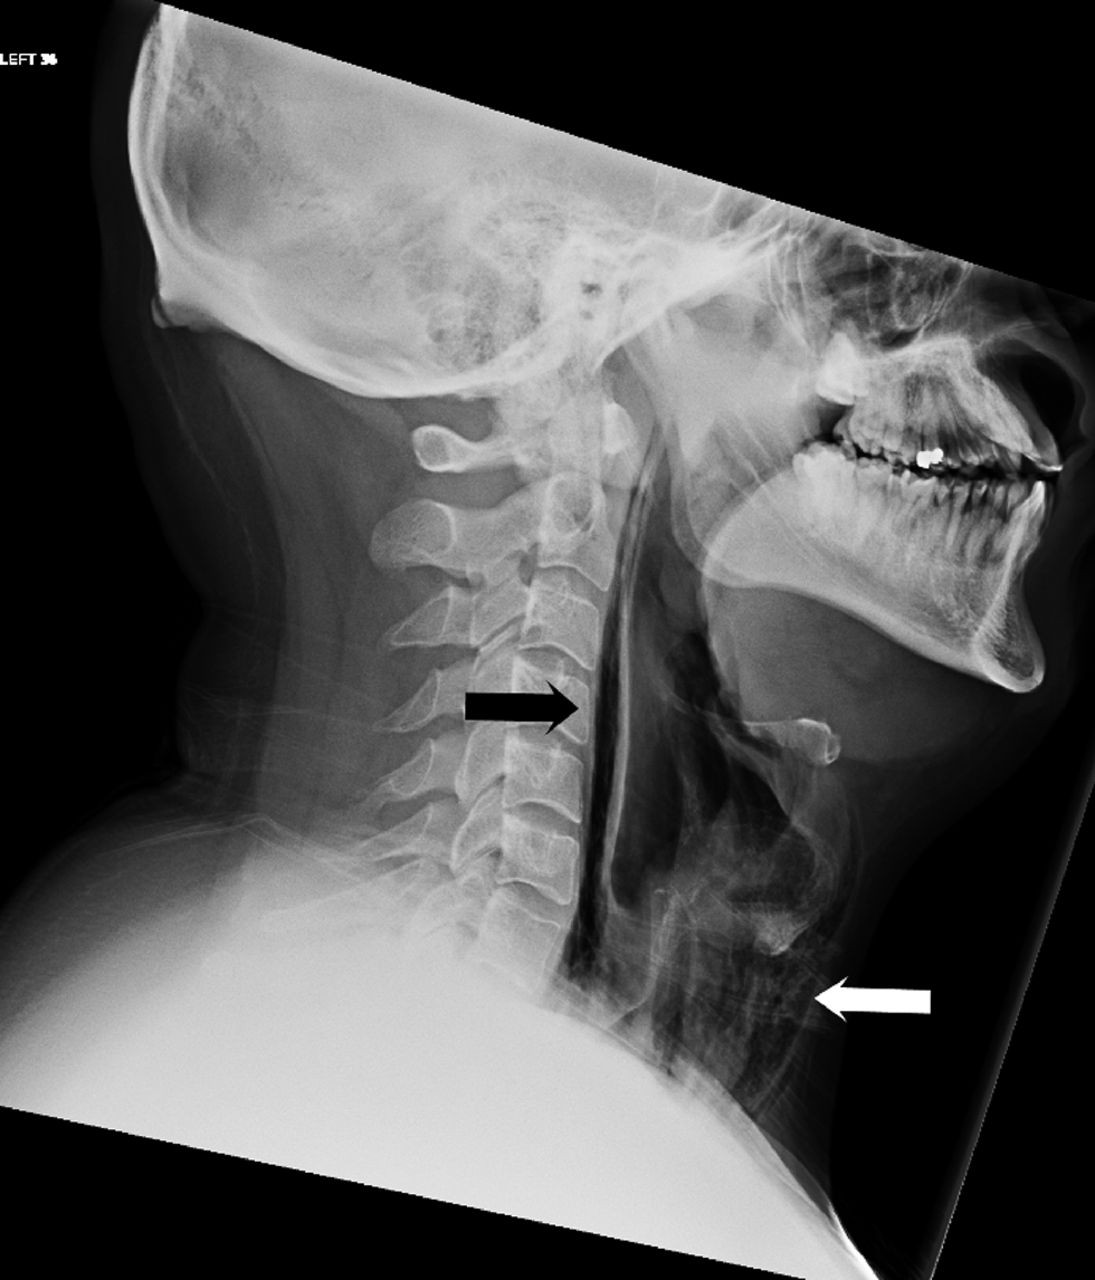

Các bác sĩ đến từ Leicester (Anh) đã đề cập đến ca cấp cứu của người đàn ông 34 tuổi bước vào phòng cấp cứu với những triệu chứng như đau nhức, khó khăn khi nuốt, nói chuyện và một cảm giác "lộm cộm" trong cổ họng bị sưng. Bệnh nhân này cho biết, những vấn đề này bắt đầu khi anh kìm nén cơn hắt hơi mạnh bằng cách bịt mũi và ngậm chặt miệng. Sau khi chụp X quang, nhận thấy có các vệt không khí ở phần ngực và cổ, các bác sĩ tiếp tục chụp CT và phát hiện ra áp lực của cơn hắt hơi bị nén kia đã xé rách mô mềm cổ họng.

Ảnh chụp X quang của bệnh nhân.